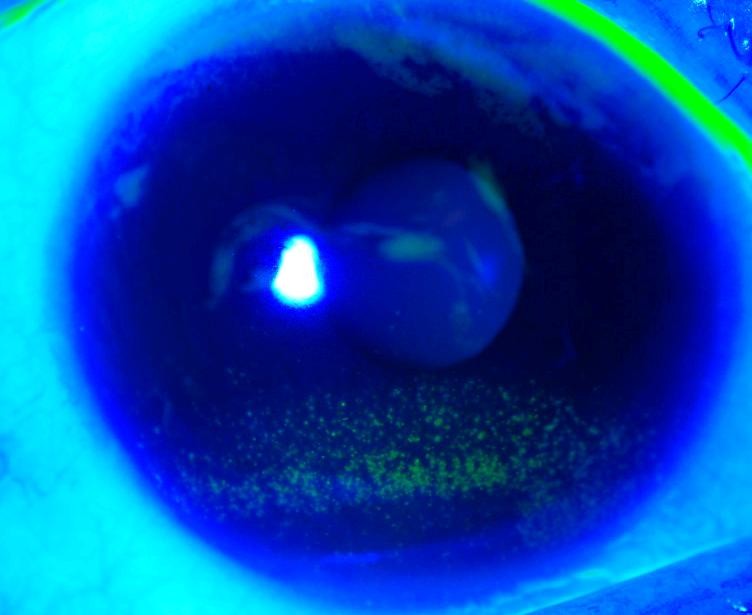

Viêm giác mạc, bệnh gây sưng, đỏ, đau, chảy rử mắt và nhạy cảm ánh sáng

Viêm giác mạc! Nếu bị đỏ mắt hoặc các triệu chứng khác của viêm giác mạc, làm một cuộc hẹn để gặp bác sĩ. Với sự quan tâm kịp thời, từ nhẹ đến vừa phải các trường hợp viêm giác mạc thường có thể điều trị.